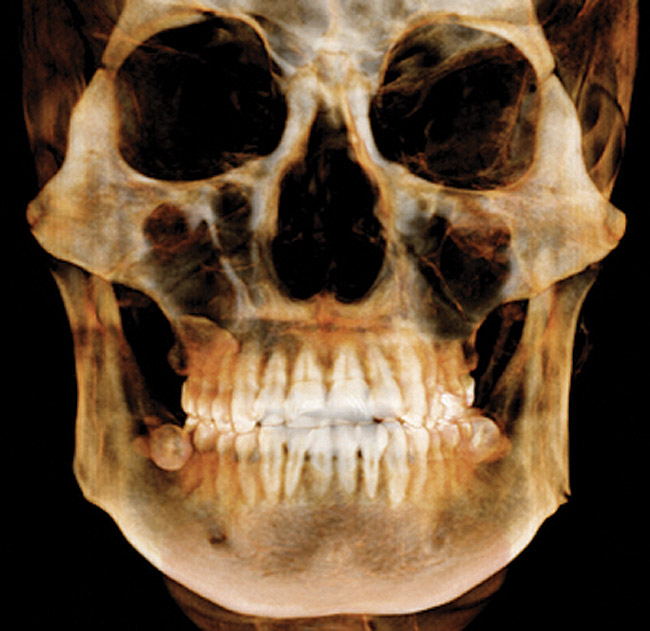

(3.) CBCT scan showing 3-dimensional rendering of both arches.

Figure 3

CBCT is indicated for the following: implant planning; developing surgical guides; general observation; finding the correct number of canals in abscessed teeth requiring endodontic treatment; in some cases, for orthodontic planning for patients with asymmetries or who need surgical procedures; for evaluation of impacted teeth or TMJ; and as an adjunct for intraoral imaging. Perhaps the most important CBCT advantage is that it offers a “third dimension” for diagnostic accuracy (Figure 3).22

Other benefits include: its short scan time; nearly immediate availability of images; compatibility with practice management software; ability to identify a variety of incidental findings, such as carotid artery calcifications; and facilitate patient communication/education. Like any imaging in dentistry, CBCT should only be used for dental purposes, but incidental findings should be recorded when they are present. CBCT should not be used specifically for screening for carotid calcification, as Duplex Doppler ultrasound is the method of choice for inspecting blood clots in the carotids. When calcification is found in the carotids, or other conditions of general health importance are found, the patient should be referred to the appropriate physician for further follow-up and treatment if needed. While there is a learning curve for reading the full image volumes, there are services available for this. Like CBCT, it is extraoral, so its advantages include that it is more comfortable for patients and can be used in patients who cannot tolerate having a sensor or film in their mouths. It can also be used when intraoral scanning is not practical—eg, for a panoramic bitewing.

It should be emphasized that CBCT should not be considered a replacement for intraoral imaging in the general practice office.19,24 In that regard, pertinent disadvantages are that it offers insufficient detail for diagnosing caries, periodontal disease, and small lesions in the bone. This is due to CBCT beam hardening artifacts and streaking caused by metallic restorations. Additional considerations include its cost, that it requires dedicated operatory space, and that CMS requires facility accreditation and CE for its reimbursement in Medicare or Medicaid patients.25 Also to consider is that it delivers a higher radiation dose than the full-mouth series (FMX) performed with round collimation.24